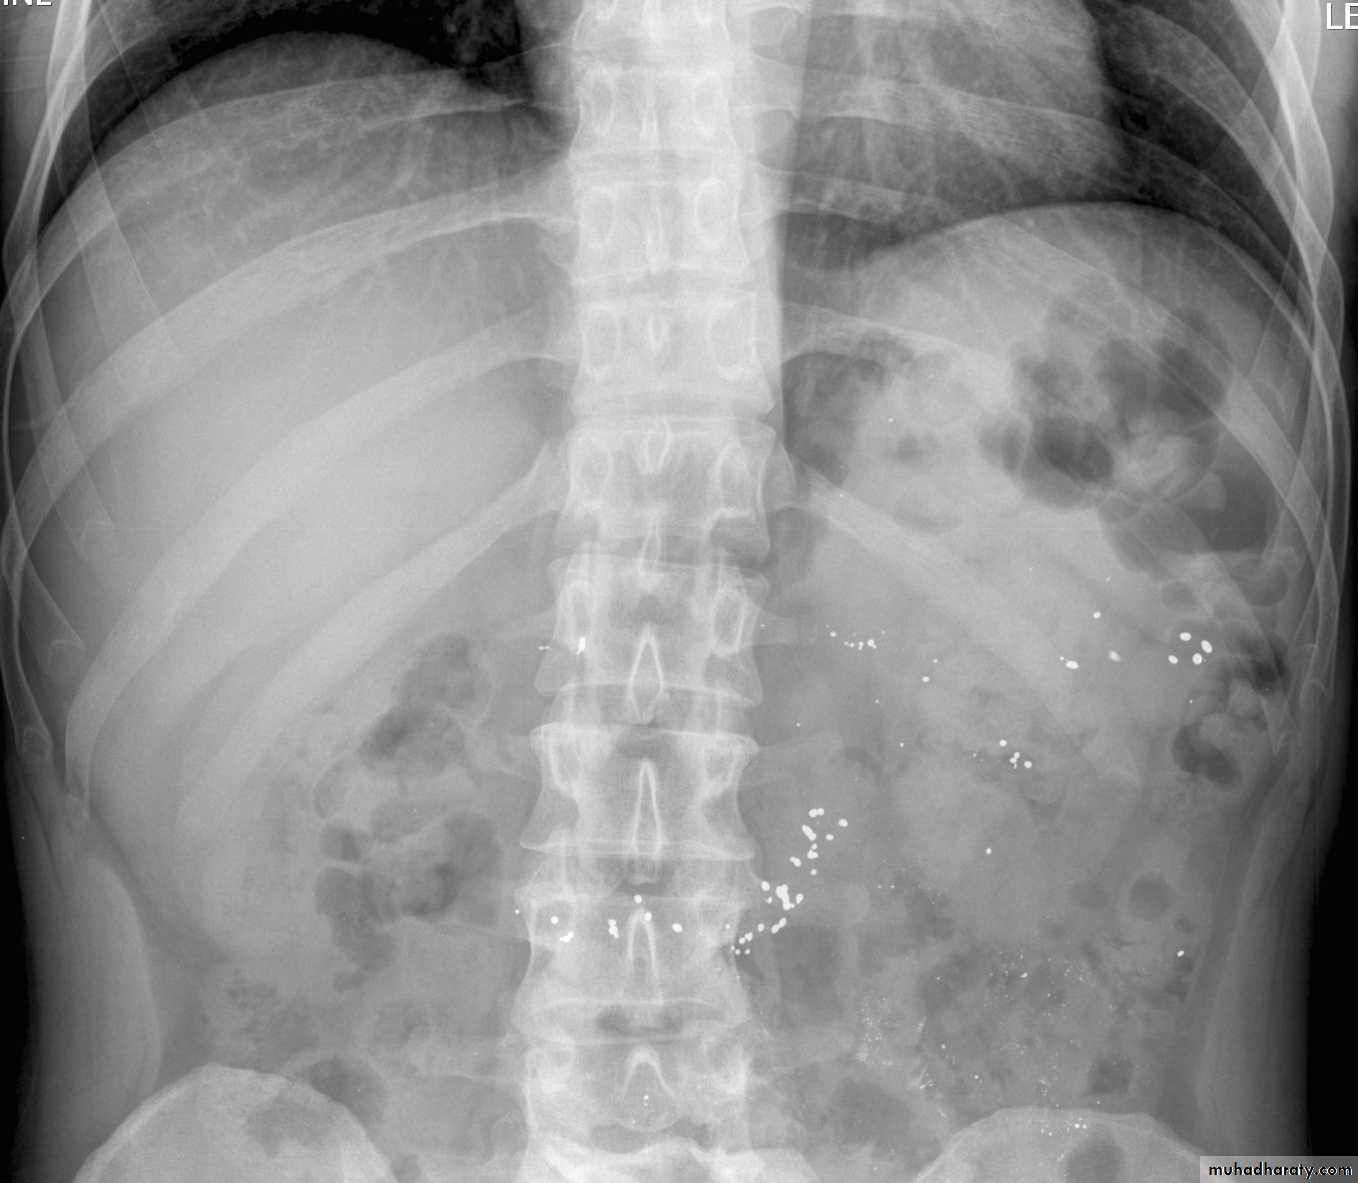

C-Radiographic examination:

-Limited role.-Lack of Radiopacity. (Undetectable by x ray).

Enteric coated formulations or restrained release could be opaque, Lead pica (in children)-CXR.

-Plain X ray Of the Abdomen.

Non cardiac pulmonary oedema.

Carbon monoxide poisoning could show lesions in brain in CT scan.